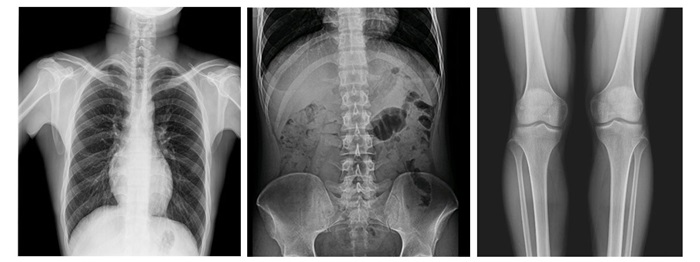

17×17英寸大幅面成像,一次曝光即可實(shí)現(xiàn)胸部、腹部全覆蓋,無需移動即可觀察整個(gè)動態(tài)過程,避免拖尾、噪聲對圖像的影響,避免漏診誤診;最高30幀/s采集幀率,動態(tài)影像更流暢,便于使醫(yī)生觀察細(xì)微病變,提高診斷的準(zhǔn)確性。